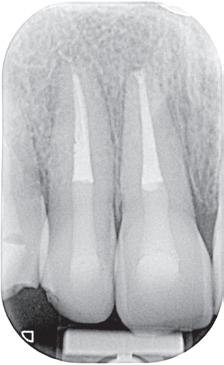

wille van necrose en de daaruit volgende symptomatische apicale parodontitis. Na klinisch onderzoek kan een buccale cervicale klasse V composietrestauratie met randlekkage en secundaire cariës weerhouden worden. De tand is intact op het occlusaal oppervlak (afbeelding 1a, b, c). Pre-operatieve peri-apicale radiografie toont een apicaal letsel met een normaal verloop van het wortelkanaal (afbeelding 2a). Eén jaar follow-up toont volledige apicale genezing aan en klinisch zijn er geen tekenen van secundaire cariës.

tie met dead-soft rotaries – om breuk te voorkomen bij de geanguleerde toegang – wordt met gehaakte sondes en ultrasone tips het meer coronaal gelegen deel van de pulpakamer gereinigd. Na activatie van het spoelmiddel (afbeelding 6a, b) kan het element worden gevuld met guttapercha en een sealer naar keuze (afbeelding 7a, b, c). Vervolgens wordt de tand hersteld met een composietrestauratie (afbeelding 8a, b, c). Eén jaar follow-up toont volledige apicale genezing aan en klinisch zijn er geen tekenen van secundaire cariës (afbeelding 9a).